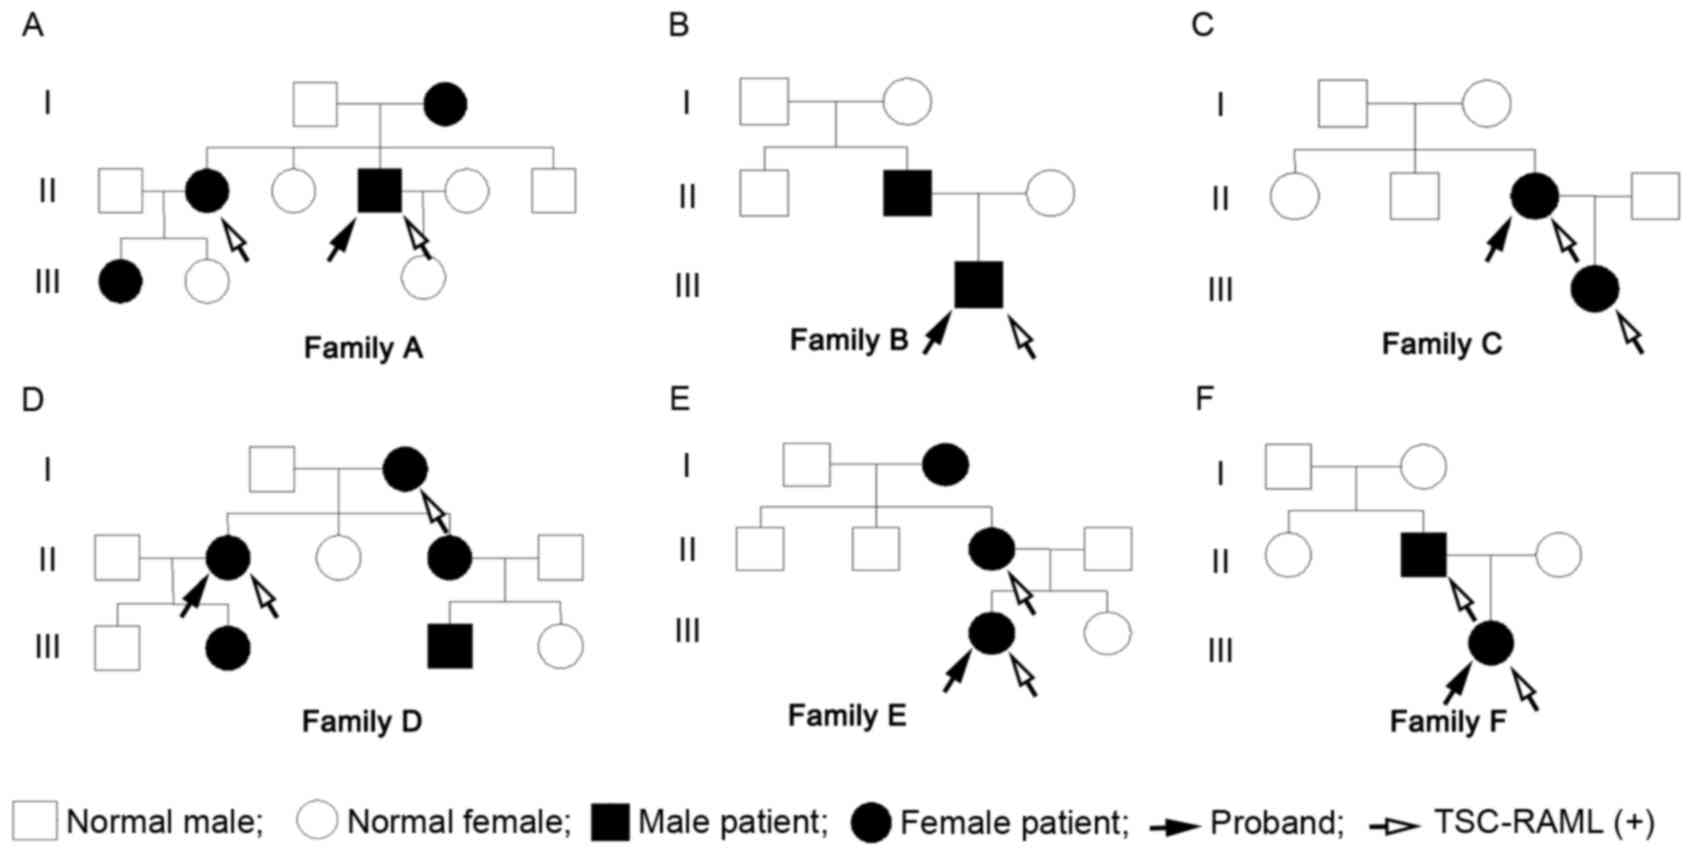

Pedigree charts of the 6 families are shown in

Fig. 1, including the 6 probands and

12 family members (female, 13; male, 5). The mean diagnostic age

was 34.22±17.73 years (Table I).

| Figure 1.(A-F) Pedigree charts of the 6

families. The pedigree charts include 18 TSC patients (female, 13;

male, 5), of which, 11 patients have been diagnosed with TSC-RAML

(female, 8; male, 3). The 6 probands are all TSC-RAML patients, of

which, just the patient from family CII is the first generation

with a pathogenic mutation, and the remaining 5 are inherited from

the previous generation. TSC-RAML, tuberous sclerosis

complex-associated renal angiomyolipoma. |

TSC is an autosomal dominant genetic disease, and

the genetic diversity of the current cohort is shown in Fig. 1. There were 18 TSC patients in the 6

pedigrees, accounting for only ~37% of subjects, and 11 with

TSC-RAML, accounting for only ~22%. Within the TSC patients,

TSC-RAML cases account for ~61%, which is similar to the data

(55–80%) reported by De Waele et al (18). The maximum diameters of TSC-RAML also